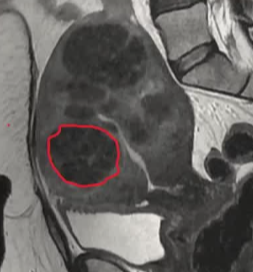

| 孤立性粘膜下子宫肌瘤 | 多发子宫肌瘤 |